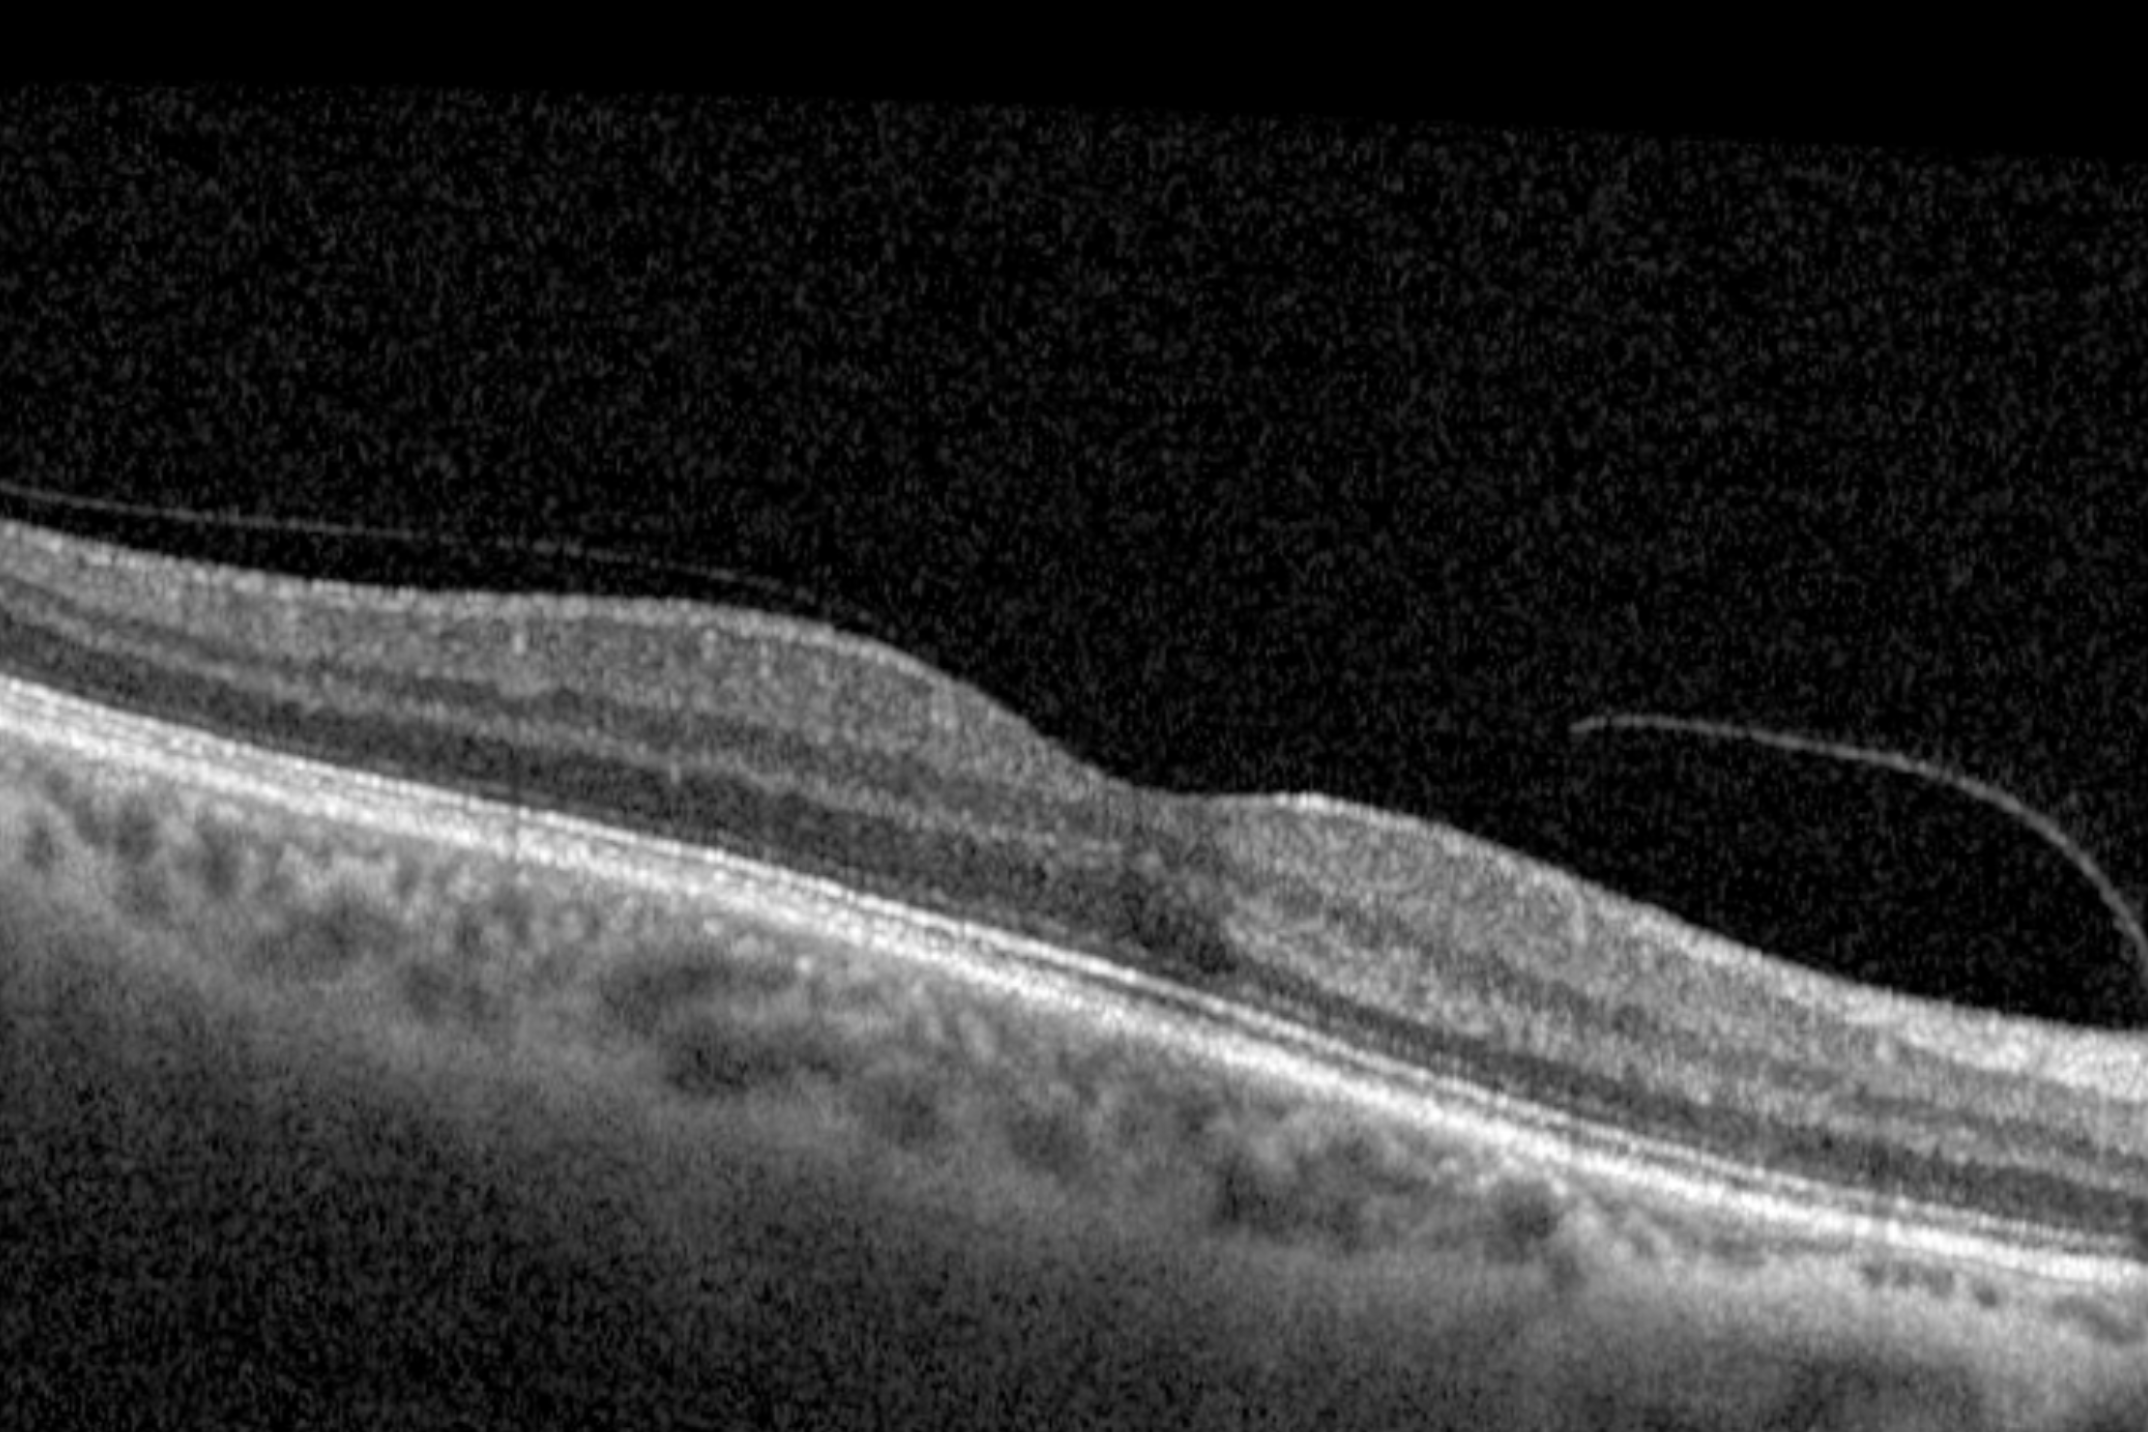

A posterior vitreous detachment is common with age and often harmless. However, because PVD can cause traction, it sometimes leads to retinal tears or detachment. Our optometrists can confirm the diagnosis with a dilated fundus exam.

We use dilated fundus exams, scleral depression, and retinal imaging to carefully examine the retina. This ensures tears or detachments are identified early.